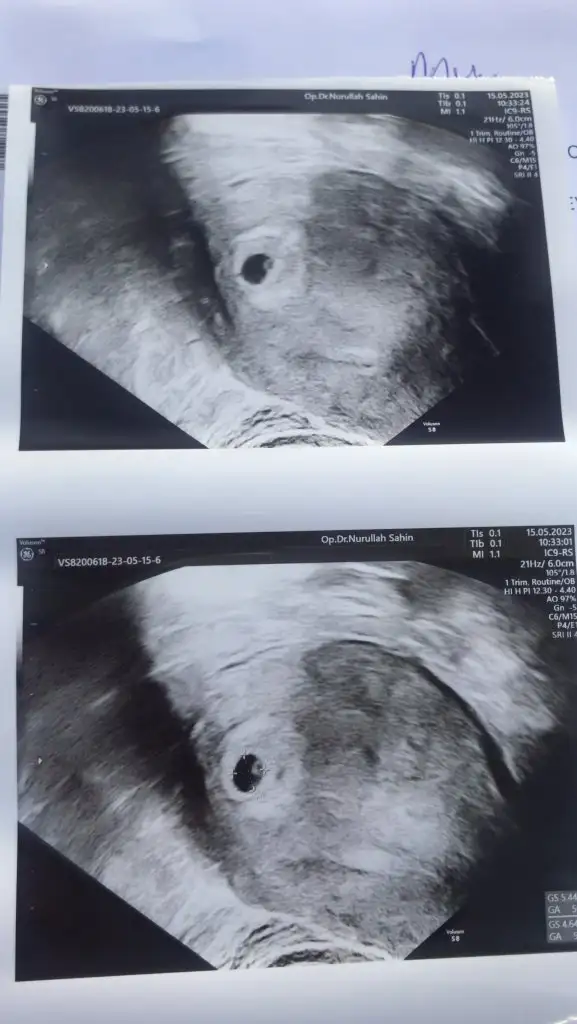

Amın, ınsallah hepimizGözünüz aydın sağlıkla alın kucağınızaBenimde tüp bebek 7+1

Vajınal kuzum . Ama 10 gun once sağdaydı sımdı solda gezıyor heraldeBu vajinal mı canım vajinal ise kıza benziyor

Soldaki kız canım sagdaki tam emin olmamakla erkek olabilirSeni birde ben darlayabilir miyim ikizlervajinal bakıldı Eki Görüntüle 3252790

Merhaab son adet döneminiz ne zaman sanırım aynıyız tarihlerde :)Bebişim gördüm kalbini duydum çok şükürnormalde 6+4 üm ama şuan 6+1 görünüyormuş ama her şey normal dedi